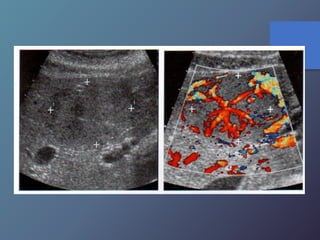

• Variable desde mas hipoecoicas hasta complejas o

Hiperecogénicas.

• Los chc pequeños son hipoecoicos, con halo periférico

fino que Corresponde a la capsula.

• Los chc de mayor diámetro, tienden a ser Heterogéneas,

complejas.

• Son hipervasculares, con vasos dismórficos.

Características Ecográficas